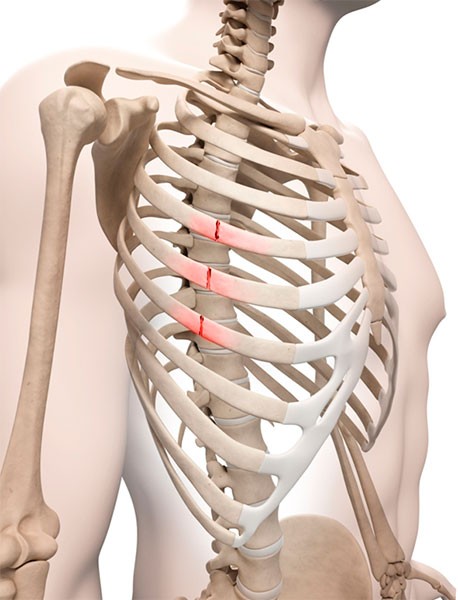

오른쪽 갈비뼈 아래 통증 원인 - 갈비뼈 골절

교통사고나 운동 중 사고, 반복적인 손상으로 인한 피로골절, 임산부의 태아 성장에 의한 골절 등 갈비뼈에 금이 가거나 부러지는 분위기이 발생됐을 경우 꾸준한 통증이 생각됩니다 보통과 다르게통증 부위에 멍, 붉어짐, 부어오름 등이 있으며 얽혀있는 가슴 부위의 흉통 역시 형성되는 경우 골절 결정을 신속하게 체크해 보아야 하고요 통증 부위에는 냉찜질을 하며 맥시멈 안정을 꾸리는게 회복을 돕는 방법인데 다발적 골절이나 내부 장기 손상 등이 의심되는 경우에는 수술적 치료가 필요할 수 있어요.